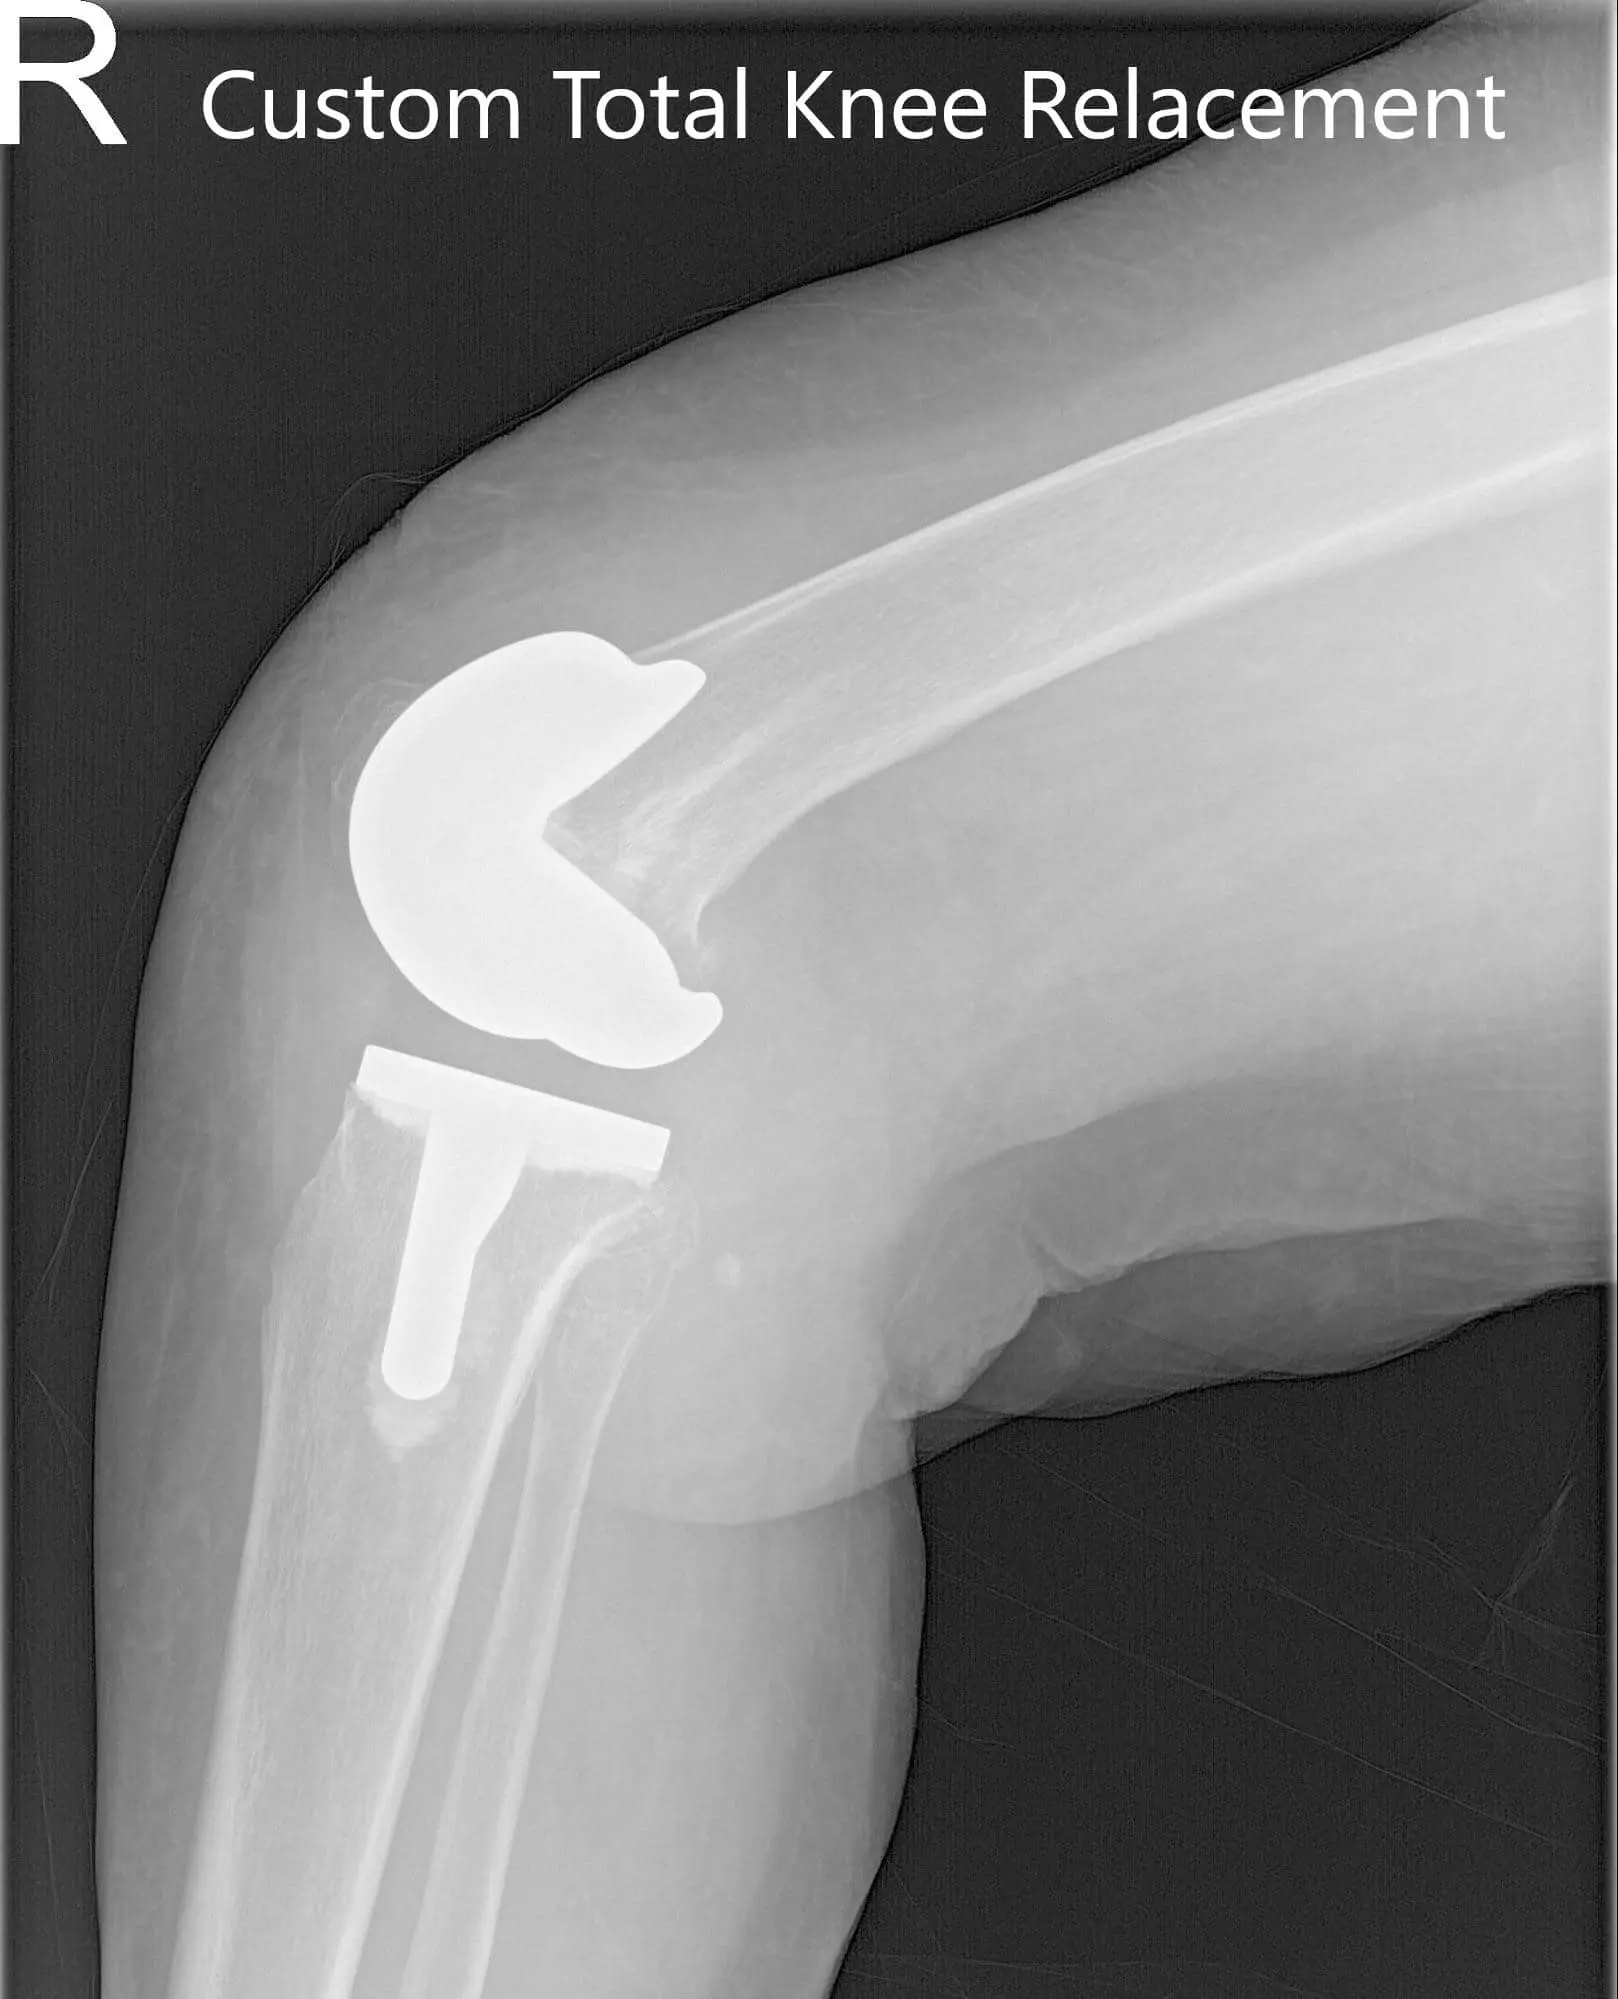

IMPLANTS USED: Custom femur and tibia bilaterally, with 10 mm polyethylene bilaterally. Right 29 mm x 6 mm patella and left 32 mm x 6 mm patella.

Postoperative X-ray showing AP and lateral views of the right and the left knee joint